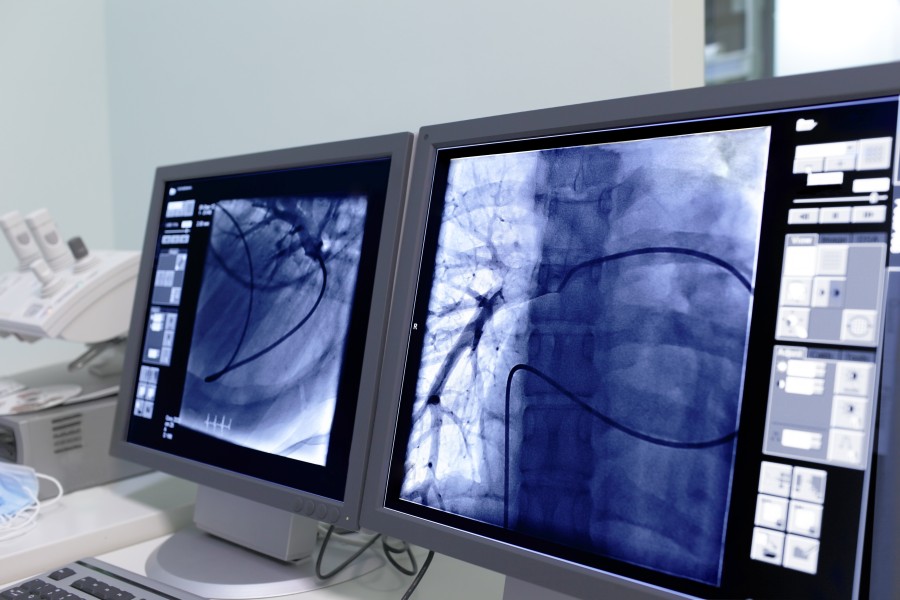

Koronarografia, nazywana też angiografią naczyń wieńcowych, to popularna metoda obrazowania naczyń wieńcowych serca, wykorzystująca promienie rentgenowskie. Aby uzyskać wyraźny obraz do tętnic przy pomocy specjalnego cewnika wprowadza się środek kontrastowy, który pochłania promieniowanie RTG, dzięki czemu naczynia są widoczne na aparaturze rejestrującej obraz.

W trakcie zabiegu uwidacznia się zarówno lewą, jak i prawą tętnicę wieńcową, a także ich odgałęzienia. Koronarografia pozwala sprawdzić, czy budowa naczyń jest prawidłowa, oraz to, czy widoczne są w nich jakieś zmiany chorobowe, które mogą utrudniać przepływ krwi.

Zabieg koronarografii wykonuje się w pracowniach hemodynamicznych lub pracowniach badań naczyniowych. Trwa około 30 minut (czasem do 1,5 godziny, gdy przypadek jest trudny) i jest dla pacjenta bezbolesny, ponieważ przeprowadza się go w znieczuleniu miejscowym. Obecnie stosuje się główne dojście naczyniowe, tzw. promieniowe (w okolicy nadgarstka). Sporadycznie wybiera się dojście udowe, znajdujące się w pachwinie.

Podczas zabiegu cewnik wprowadzany jest do tętnicy obwodowej. Gdy znajdzie się w odpowiednim miejscu, podawany jest środek kontrastowy, który miesza się z krwią. W tym momencie pacjent może odczuwać ciepło. Cały ten proces jest nagrywany i może być przez kardiologa odtwarzany, aby ocenić budowę i stan naczyń, a także pracę serca. Po usunięciu cewnika w miejscu wkłucia zakłada się opatrunek uciskowy.